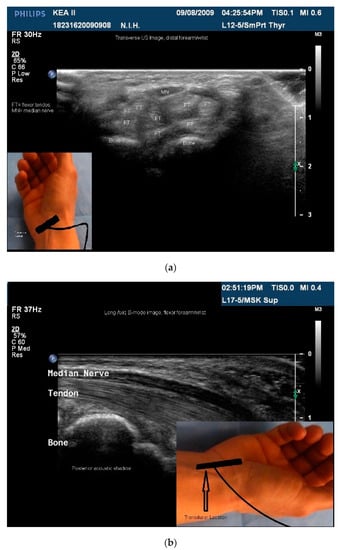

- Skeletal muscle: The sonoacoustic appearance of muscle is a mix of hyperechoic intramuscular connective tissue and hypoechoic contractile fascicles. In long axis or longitudinal view, the contractile elements and connective tissue of skeletal muscles appear as hypoechoic or hyperechoic linear bands or streaks. In transverse view, the muscle has a speckled hypo/hyperechoic appearance from the mix of contractile fascicles and connective tissue viewed in short axis [47,48,49,50]. Figure 1a,b.

- Nerves: are less hyperechoic or fibrillar than tendon. With a high frequency transducer (≥12 mHz), nerves fascicles can be visualized. In longitudinal view, the epineurium will appear hyperechoic compared to the relatively hypoechoic nerve fascicles giving the nerve the appearance of a “railroad track”. In transverse view the relatively hyperechoic epineurium surrounds the hypoechoic fascicles giving the nerve a speckled appearance [49,51] (Figure 2a,b).